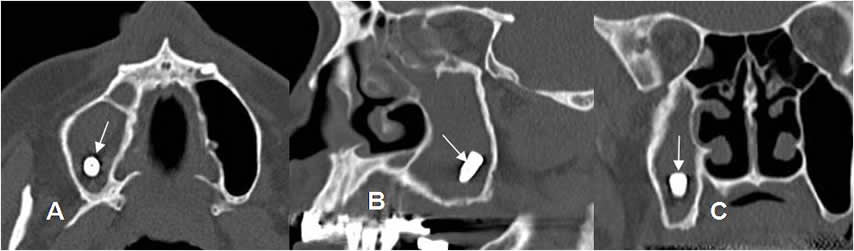

Fig 20 B. Raíces retenidas.

A y B: TAC reconstrucción panorámica y C: TAC reconstrucción coronal.

Ausencia de molares y premolares a nivel bilateral, con fragmentos de raíces retenidas.